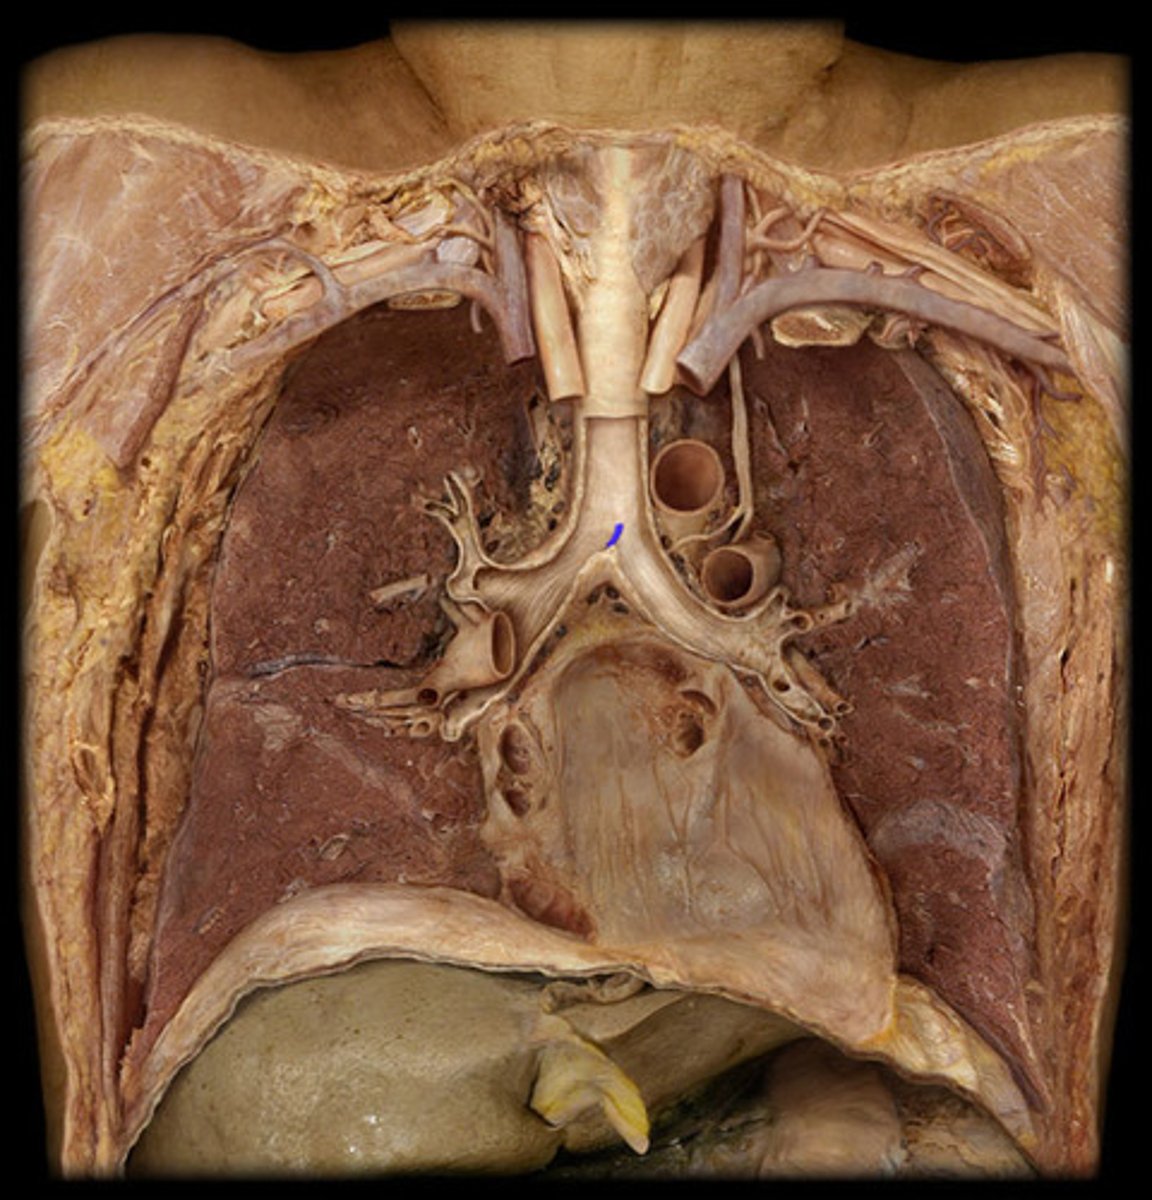

Trachea

Carina

Right Primary Bronchus

Left Primary Bronchus

Secondary Bronchus

Tertiary Bronchus